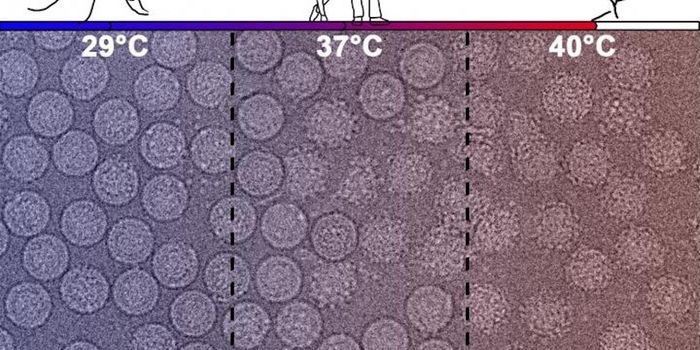

APR 25, 2022MicrobiologyWhen a pathogen invades the body, the immune system has to mount a response, which involves inflammation. But inflammati ...